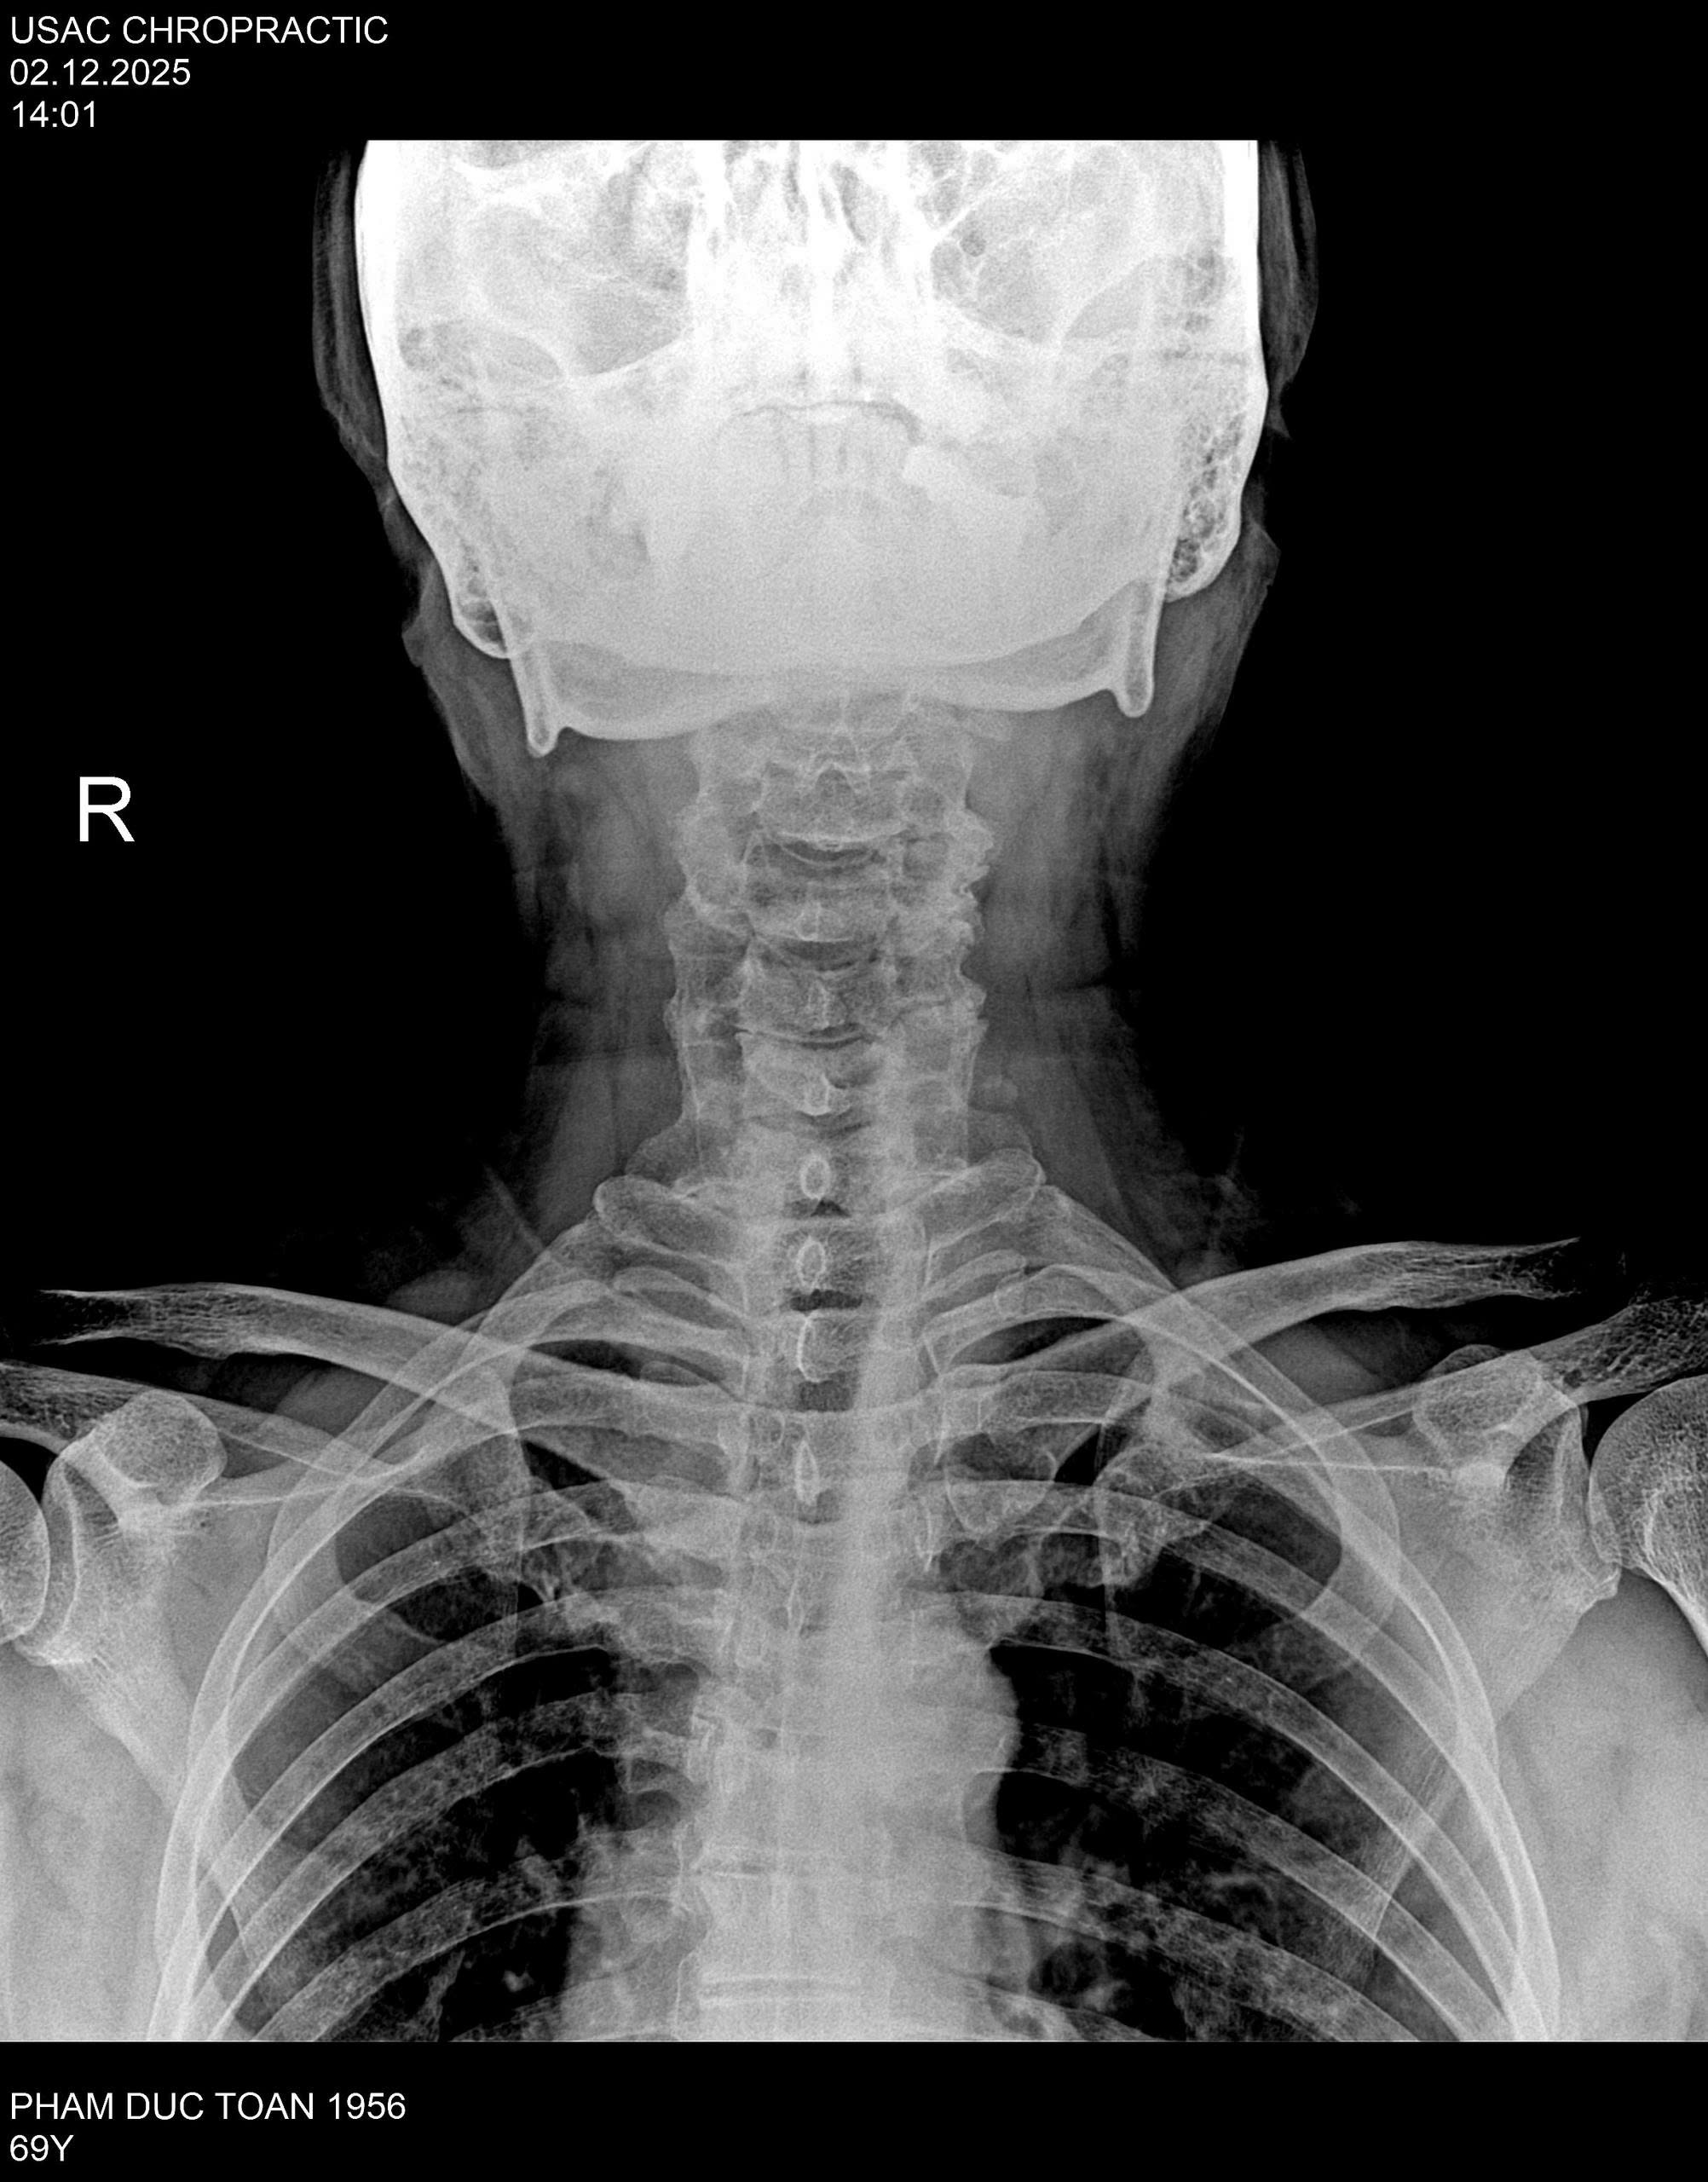

Thế nhưng, thoái hóa cột sống cổ C5–C6 đã khiến chú Toàn nhiều lần rơi vào trạng thái bất lực.

Cơn đau âm ỉ từ cổ lan xuống vai, cánh tay, thỉnh thoảng nhói ra sau lưng… khiến từng giờ đứng lớp trở nên nặng nề, sinh hoạt hằng ngày cũng bị ảnh hưởng.